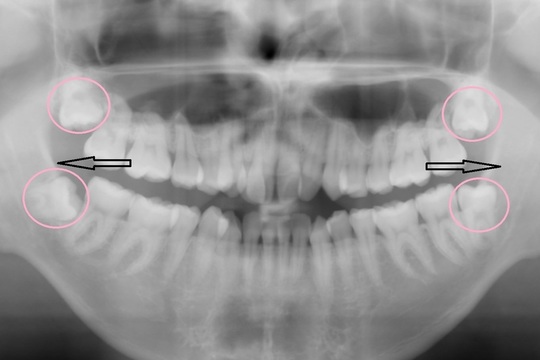

このレベルの叢生であれば、誰しも抜歯矯正を考えると思います

しかし今回は、抜歯矯正を行うと後のかみ合わせなどのリスクが高く感じたため

親知らずの抜歯にとどめ、奥歯をそのスペースに送ることで

前歯が収まるスペースを得ることを考えました

下のレントゲンにイメージを図示しています

もう一つ大きな注意点があります

初診時に大きく中に入っていた上の右2番目(向かって左側2番目)の前歯

これを理想と思われる位置にもっていきたかったのですが

初診時のCT(3Dのレントゲン)を細かく分析すると

理想の位置に移動させてしまうと

最悪歯が骨から抜けてしまい抜歯に至る可能性がありました

(専門用語でフェネストレーションといいます)

矯正治療をしたことで抜歯に至るというのは本末転倒です

今回は理想の位置よりもわずかに中に入った位置で矯正終了となることを

事前に患者さまにご了承いただいてからスタートしております

現在ではCTとクリンチェックを結合することができるので

もっとわかりやすく確認できるようになっていますが

下にCTの画像を載せておきます

〇部分が骨がないところ 矢印の歯を理想の位置までは動かせません